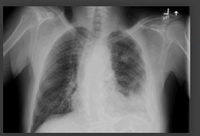

Neumonía adquirida en la comunidad en adultos (no COVID-19)

Radiografía de tórax posterior-anterior que muestra consolidación del lóbulo superior derecho en un paciente con neumonía adquirida en la comunidad

Durrington HJ, et al. Recent changes in the management of community acquired pneumonia in adults. BMJ 2008;336:1429.